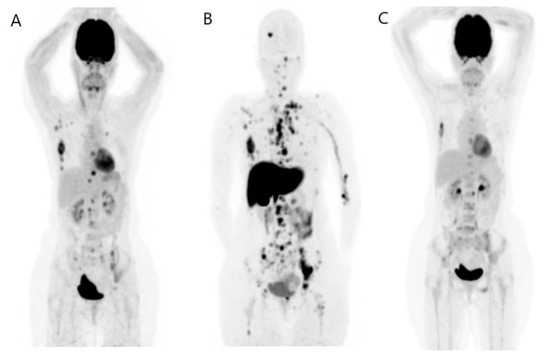

- Zhang, F.C.; Xu, H.Y.; Liu, J.J.; Xu, Y.F.; Chen, B.; Yang, Y.J.; Yan, N.N.; Song, S.L.; Lin, Y.M.; Xu, Y.C. 18F-FDG PET/CT for the early prediction of the response rate and survival of patients with recurrent or metastatic breast cancer. Oncol. Lett. 2018, 16, 4151–4158. [Google Scholar] [CrossRef]

- Hildebrandt, M.G.; Naghavi-Behzad, M.; Vogsen, M. A role of FDG-PET/CT for response evaluation in metastatic breast cancer? Semin. Nucl. Med. 2022, 52, 520–530. [Google Scholar] [CrossRef]

- Dose Schwarz, J.; Bader, M.; Jenicke, L.; Hemminger, G.; Jänicke, F.; Avril, N. Early prediction of response to chemotherapy in metastatic breast cancer using sequential 18F-FDG PET. J. Nucl. Med. 2005, 46, 1144–1150. [Google Scholar]

- Cachin, F.; Prince, H.M.; Hogg, A.; Ware, R.E.; Hicks, R.J. Powerful prognostic stratification by [18F]fluorodeoxyglucose positron emission tomography in patients with metastatic breast cancer treated with high-dose chemotherapy. J. Clin. Oncol. 2006, 24, 3026–3031. [Google Scholar] [CrossRef]

- Riedl, C.C.; Pinker, K.; Ulaner, G.A.; Ong, L.T.; Baltzer, P.; Jochelson, M.S.; McArthur, H.L.; Gönen, M.; Dickler, M.; Weber, W.A.; et al. Comparison of FDG-PET/CT and contrast-enhanced CT for monitoring therapy response in patients with metastatic breast cancer. Eur. J. Nucl. Med. Mol. Imaging 2017, 44, 1428–1437. [Google Scholar] [CrossRef]

- Goulon, D.; Necib, H.; Henaff, B.; Rousseau, C.; Carlier, T.; Kraeber-Bodere, F. Quantitative Evaluation of Therapeutic Response by FDG-PET-CT in Metastatic Breast Cancer. Front. Med. 2016, 3, 19. [Google Scholar] [CrossRef] [PubMed]

- Taralli, S.; Lorusso, M.; Scolozzi, V.; Masiello, V.; Marazzi, F.; Calcagni, M.L. Response evaluation with 18F-FDG PET/CT in metastatic breast cancer patients treated with Palbociclib: First experience in clinical practice. Ann. Nucl. Med. 2019, 33, 193–200. [Google Scholar] [CrossRef] [PubMed]